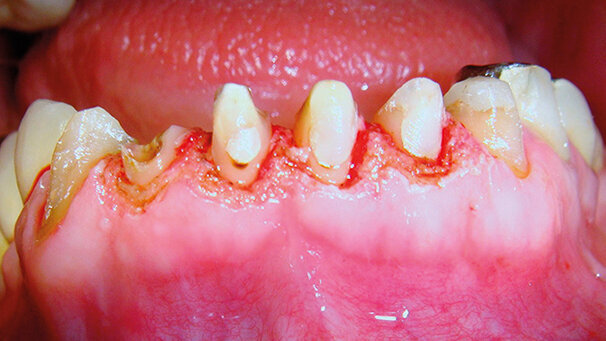

Il paziente è un maschio di 52 anni, che necessita di una riabilitazione protesica del gruppo frontale inferiore dall’elemento 4.3 al 3.3. La Fig. 1 mostra infatti la necessità di armonizzare i profili gengivali dei centrali inferiori, di ricostruire la radice dell’elemento 4.2 e di posizionare il provvisorio in resina già confezionato prima della riabilitazione finale. Pertanto, con una ridotta infiltrazione di anestesia loco-regionale, si procede all’intervento di gengivoplastica con laser a diodo 980 (KaVo MASTER lase). L’intervento è stato effettuato con il laser settato a 0,8 W in modalità iperpulsata, secondo le caratteristiche proprie dell’apparecchio, in modo da ottenere un’eccellente rapidità di taglio con una ridotta interazione laser-tessuto; la Fig. 2 mostra l’immediato post-operatorio dove sono evidenti le radici dei denti trattati con i profili gengivali ridisegnati, ma soprattutto si nota l’assenza di fenomeni di carbonizzazione. Il provvisorio in resina è stato immediatamente posizionato. A distanza di 7 giorni (Figg. 3a, 3b, 3c), senza aver ribasato appositamente il provvisorio proprio al fine di rendere più evidente l’effetto del nostro trattamento chirurgico mediante laser a diodo, i tessuti gengivali si presentano in uno stato di guarigione pressoché completo, ma soprattutto senza segni di flogosi residua né di retrazione gengivale indesiderata (Figg. 4a, 4b, 4c). Si è proceduto pertanto immediatamente alla presa di impronta per la riabilitazione finale mediante corone in zirconia-ceramica (Fig. 5).